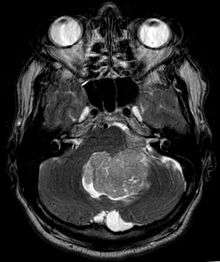

Ependymoma is a tumor that arises from the ependyma, a tissue of the central nervous system. Usually, in pediatric cases the location is intracranial, while in adults it is spinal. The common location of intracranial ependymoma is the fourth ventricle. Rarely, ependymoma can occur in the pelvic cavity.

Ependymomas are composed of cells with regular, round to oval nuclei. There is a variably dense fibrillary background. Tumor cells may form gland-like round or elongated structures that resemble the embryologic ependymal canal, with long, delicate processes extending into the lumen; more frequently present are perivascular pseudorosettes in which tumor cells are arranged around vessels with an intervening zone consisting of thin ependymal processes directed toward the wall of the vessel.[2]

Ependymoma tumors

Ependymomas make up about 5% of adult intracranial gliomas and up to 10% of childhood tumors of the central nervous system (CNS). Their occurrence seems to peak at age 5 years and then again at age 35. They develop from cells that line both the hollow cavities of the brain and the canal containing the spinal cord, but they usually arise from the floor of the fourth ventricle, situated in the lower back portion of the brain, where they may produce headache, nausea and vomiting by obstructing the flow of cerebrospinal fluid. This obstruction may also cause hydrocephalus. They may also arise in the spinal cord, conus medularis and supratentorial locations.[4] Other symptoms can include (but are not limited to): loss of appetite, difficulty sleeping, temporary inability to distinguish colors, uncontrollable twitching, seeing vertical or horizontal lines when in bright light, and temporary memory loss. It should be remembered that these symptoms also are prevalent in many other illnesses not associated with ependymoma.